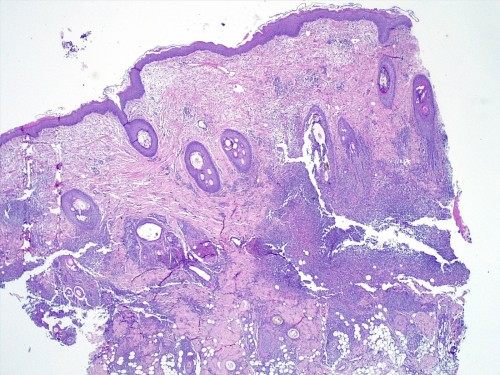

– les biopsies cutanées (LAPVSO) concluent à de sévères lésions de dermohypodermite neutrophilique avec furonculose et lésions hypodermiques ponctuelles de vascularite leucocytoclasique (Photos 4 à 9)

Examen histopathologique montrant un épiderme intact ou sévèrement ulcéré. Dans le derme, on observe un œdème superficiel ainsi que de multiples foyers inflammatoires non encapsulés, souvent à point de départ folliculaire ou périfolliculaire, pouvant fusionner, rompre les follicules pileux et s’étendre dans l’ensemble du derme voire gagner l’hypoderme. Ces foyers sont caractérisés par l’accumulation de granulocytes neutrophiles qui semblent altérés et qui dissèquent les fibres de collagène autour du follicule pileux ainsi que la paroi folliculaire et la lumière folliculaire. De nombreuses plages inflammatoires contiennent des tiges pilaires nues. L’infiltrat peut s’étendre dans l’hypoderme, mais ce dernier est surtout caractérisé par un épaississement des septa conjonctifs interlobulaires du tissu adipeux avec œdème, accumulation d’un matériel fibrinoïde, dilatation vasculaires des vaisseaux lymphatiques et des structures vasculaires de petit calibre, les vaisseaux lymphatiques étant encombrés d’un matériel inflammatoire fibrino-leucocytaire. Il peut exister des images focales de vascularite leucocytoclasique au sein de l’hypoderme.